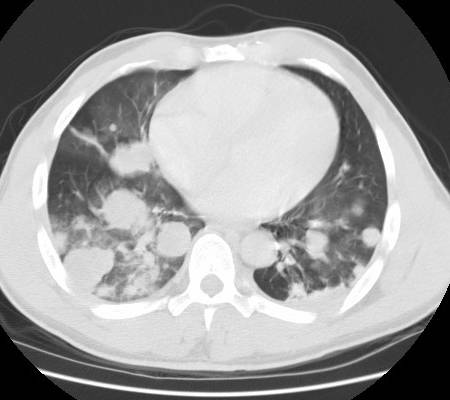

weekly clinical round for undergraduate from 8 to 11 AM during which interpretation of CHEST X rays was done for all cases of cardiothoracic surgery, gived by 2 staf member for 3 months